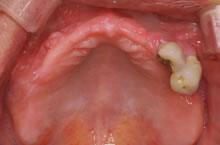

【1】治療前写真1

他院で3年前に上アゴ全体にインプラント6本を入れその上に固定性入れ歯を装着されておりましたが、経過不良に伴い1年経たずに2本以外は抜け落ちたため、事後の改善と再治療を希望され受診されました。どうしても義歯ではなく、インプラント治療を行い満足行く楽しい食生活をしたいとのご希望でした。

残りのインプラント2本も揺れていました。 CT検査の結果により、左右上奥のインプラントを支える骨が不足していました。そのため、揺れているインプラント撤去と同時に、支えるの骨を増やす特殊な手術、上顎洞底挙上術(サイナスリフト)を併用し、じっくり治療していけばインプラント治療が可能になることを説明しました。ご本人も術後の回復された後の状態がイメージでき、治療を希望され開始しました。 現在、丈夫な骨を再建する特殊な治療もインプラント6本を埋入終了し、仮歯を装着して美味しく食事をされています。 今後、下アゴにも15年以上前に入れてご自分の歯と連結されていますが揺れている経過が危ういインプラントがあるため、撤去し、再度、インプラントを予定しています。